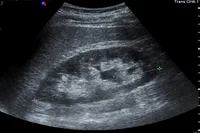

La imagen corresponde a:

Ultrasonido Renal Normal

Doble sistema colector

Banda fibrosa en seno renal

Masa renal en polo

¿Que hallazgos encuentras en el ultrasonido de este paciente?

Quiste parapielico

Poliquistosis renal

Hidronefrosis

Litiasis renal